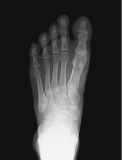

X-ray of right hip osteoporosis, age 54